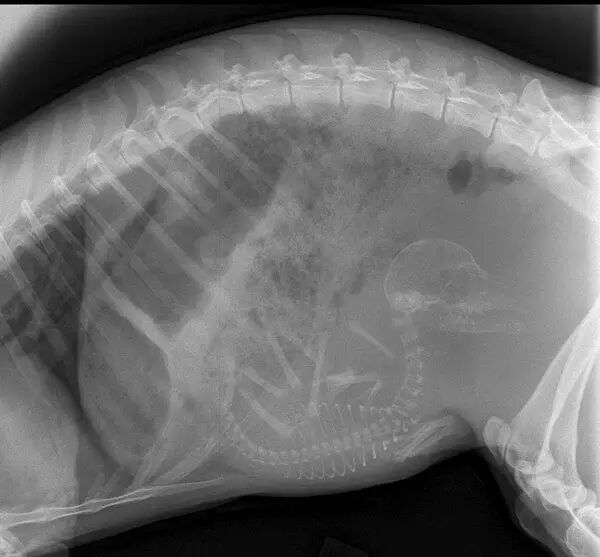

怀孕是一件神圣而又带有神秘色彩的事,她预示着新生命的来临。在动物世界,怀孕是怎样的一种奇迹,以下 14 种动物在怀孕期间的 X 线图片,我们可以通过全新的影像视角探查一番。

• 乌龟